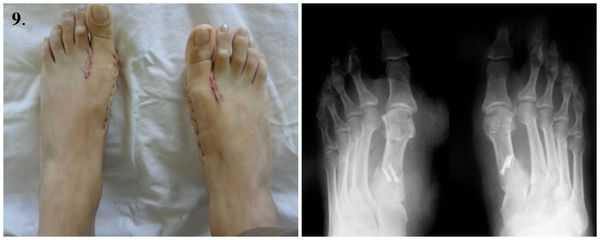

Этапы операции по реконструкции переднего отдела стопы при помощи миотенопластики:

1. Стопы до операции.

9. Стопы сразу после операции.